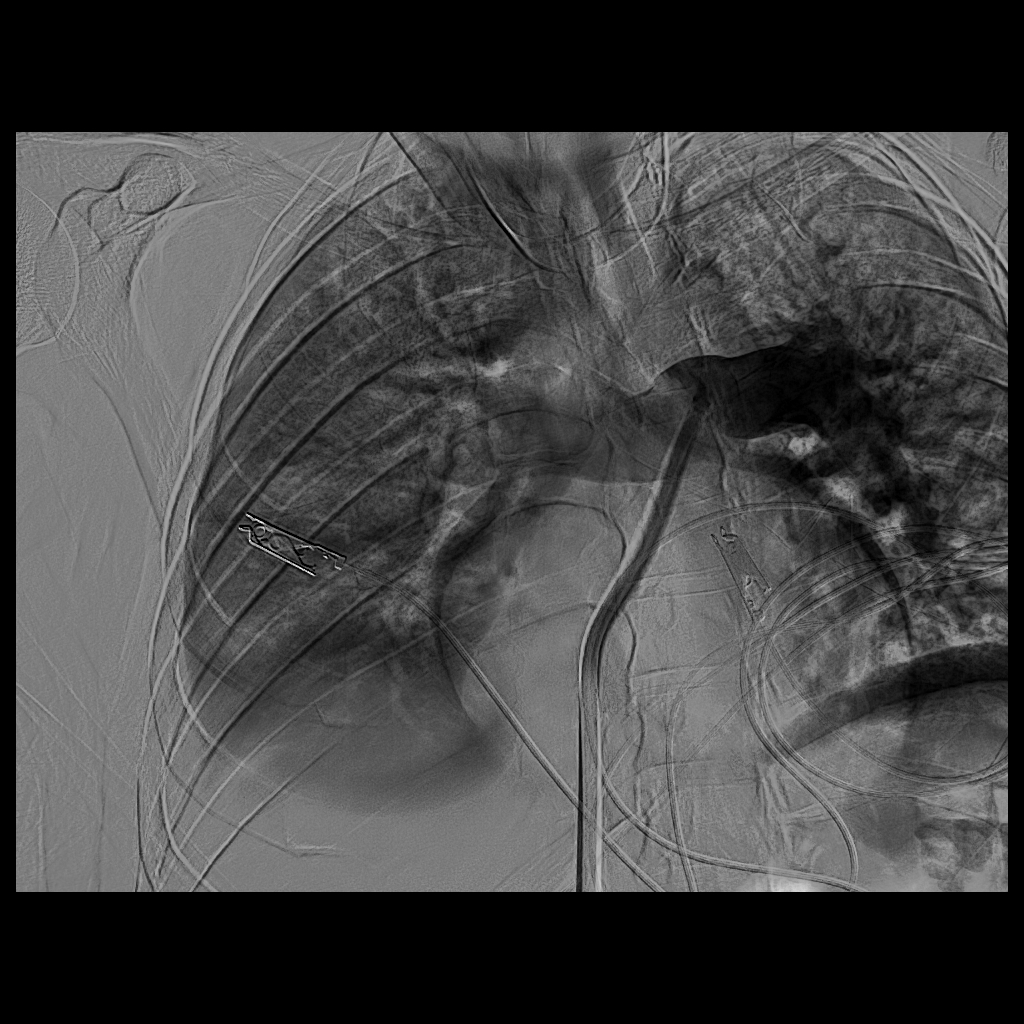

سجل مجمع الدمام الطبي أحد مكونات تجمع الشرقية الصحي ، إنجازاً طبياً نوعياً بعد نجاح فريق الأشعة التداخلية في إنقاذ حياة مريض كان يعاني من جلطة رئوية حادة وكبيرة شكّلت خطراً مباشراً على حياته ، وذلك باستخدام تقنية طبية متقدمة دون الحاجة إلى جراحة قلب مفتوح .

وكان المريض قد نُقل بشكل إسعافي من أحد المستشفيات وهو في حالة حرجة ، نتيجة معاناته من ضيق شديد في التنفس وانخفاض حاد في مستوى الأكسجين ، إثر انسداد كامل في الشريان الرئوي الرئيسي بسبب خثرات وريدية عميقة ظهرت بعد خضوعه لعملية منظار لمفصل الركبة.

وبفضل سرعة الاستجابة وجاهزية فريق الأشعة التداخلية جرى التدخل العلاجي العاجل وفتح الشريان الرئوي وسحب الجلطة بالكامل بدقة عالية ، ما أدى إلى تحسّن فوري في العلامات الحيوية واستقرار الحالة دون تسجيل أي مضاعفات.